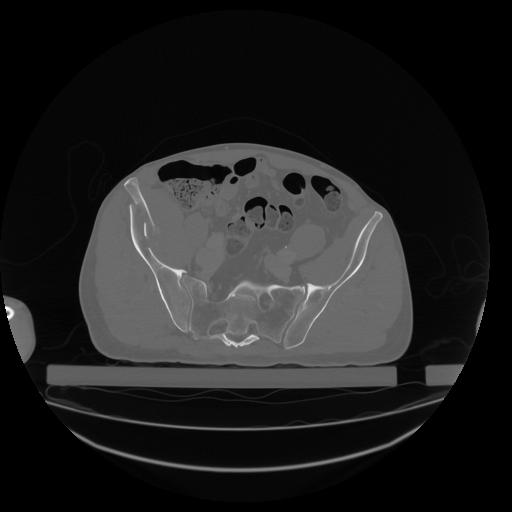

34 CUERPO,CE,Vol,1.0,CUERPO,,